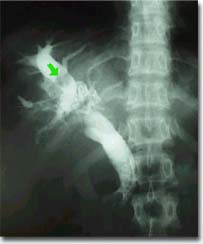

肝内胆管妇科会不会很严重,对人体伤害有多大?所谓肝内胆管妇科是指左、右肝胆管及其分支部分的妇科。肝内胆管妇科可分为原发必和继发性两种,而以后者较为常见。左外叶和右后叶的胆管内多见。可能与肝内胆管的解剖特点有关。多为胆色素妇科,常为多发。其大小、形态不一,肝胆管常有局限性狭窄和局部囊状扩张。

肝内胆管妇科会成为热点话题绝非危育耸听,胆石症真的是一种时髦病,我们看到不少人捧着药罐子天天喝药,还有人四处求医,打探治疗胆石症的秘方。胆石症又不是一种只有现代人才得的病,古埃及的法老们就为胆石症所困扰,可见其历史悠久。但是胆石症在当今如此之多,以致于成年人尤其是女性只要经常感到上腹沉重、腰背及右肩酸胀、打呃、嗳气,就应该警惕患上了胆石症。